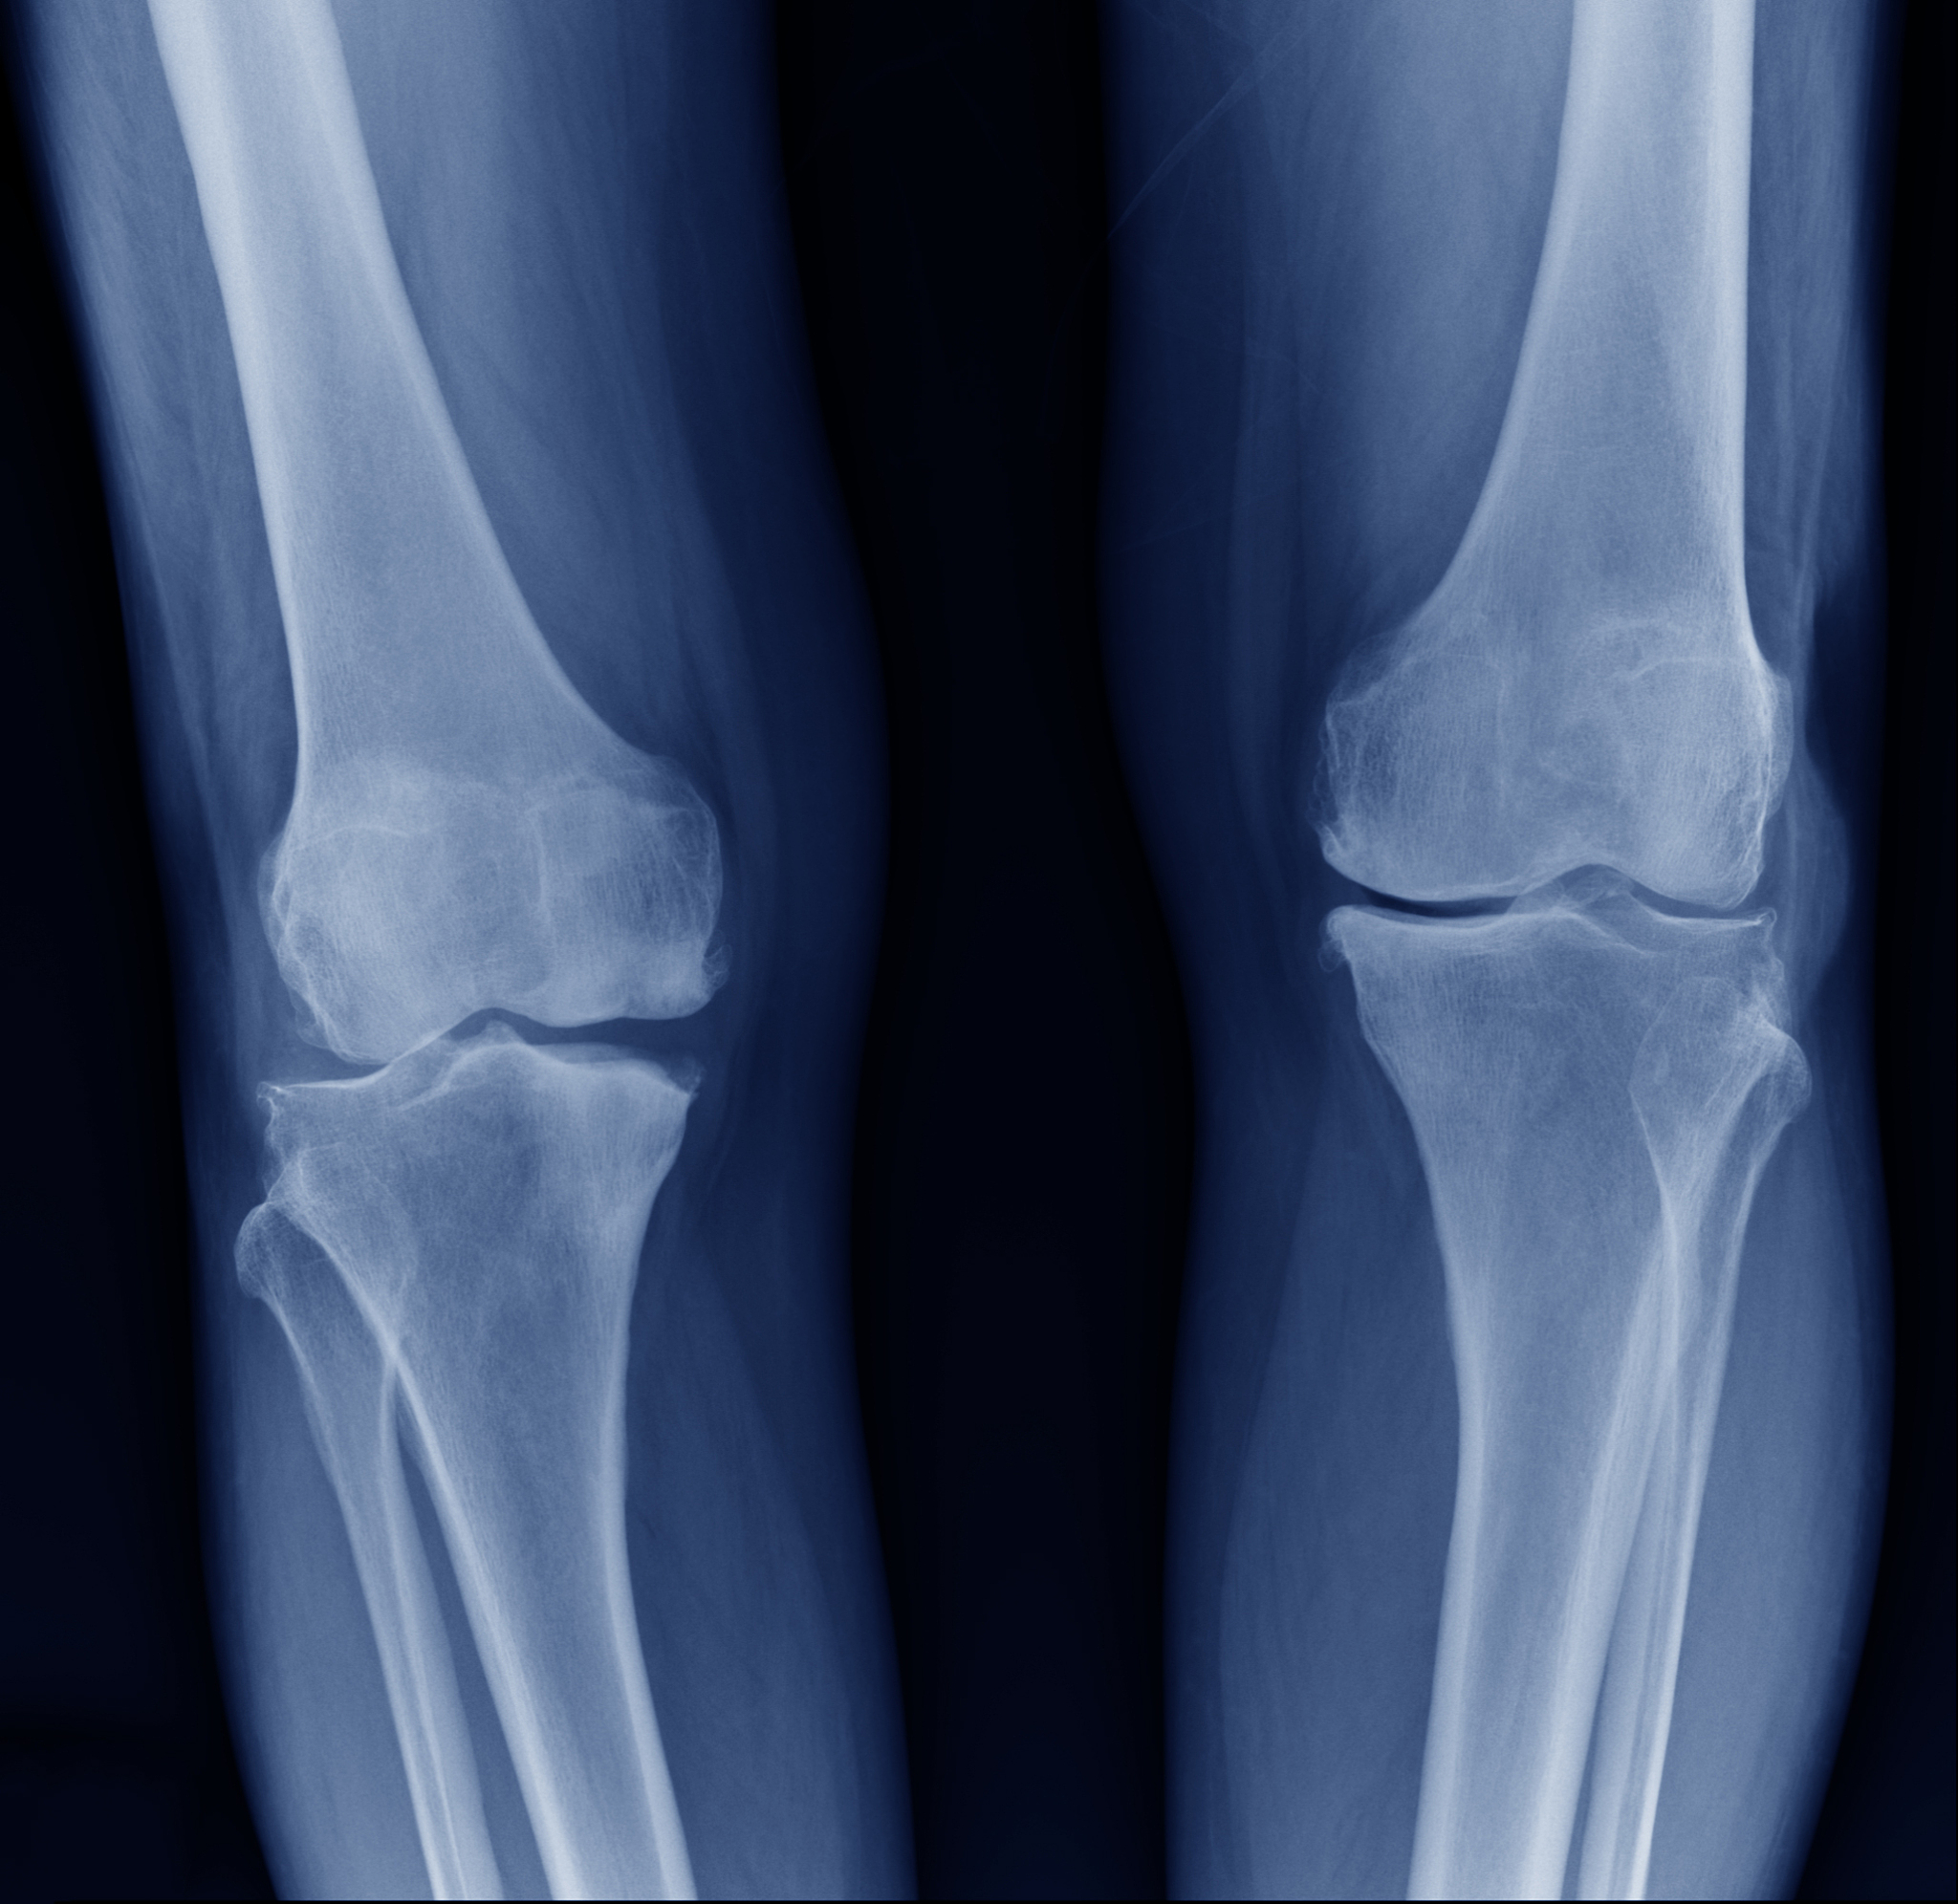

2. 影像学检查:X线是最常用的影像学检查方法,可以明确诊断胫骨平台骨折及其类型。后外侧塌陷的胫骨平台骨折通常表现为胫骨平台的后外侧部分向下塌陷,形成一个凹陷或凹槽。有时候,CT扫描可能需要用于进一步评估骨折的复杂性和伴随的软组织损伤。

3. 分类和治疗:胫骨平台骨折按Schatzker分类可分为6个类型,其中后外侧塌陷的骨折通常属于类型V或VI。治疗方法包括保守治疗和手术治疗。保守治疗适用于骨折稳定、无明显移位或老年患者。手术治疗常常需要进行骨折复位、内固定和修复软组织损伤。